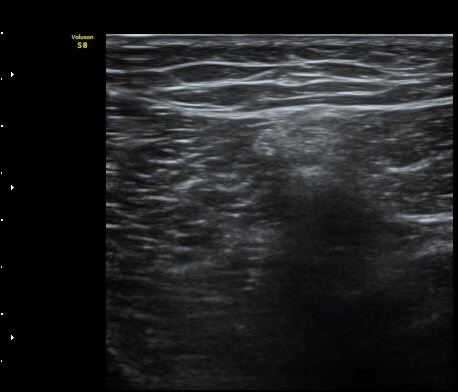

¹«¸­ ³»Ãø Á¾´Ü¸é°Ë»ç»ó ½ÉÇÑ °ñ±Ø°ú ¹Ý¿ù»ó¿¬°ñ Ç¥ÃþÀ¸·Î µ¹ÃâÀÌ °üÂûµÊ(»çÁø 1)